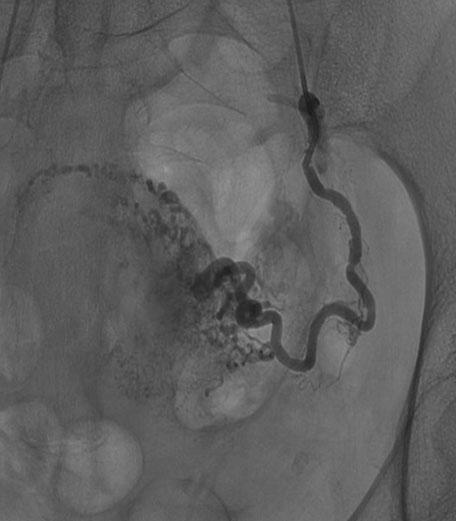

The case was discussed in a multidisciplinary meeting together with interventional radiologists. According to ultrasound features suggesting an acquired UAVM and to absence of bleeding, a conservative management with follow-up was adopted. Outpatient follow-up examination after two weeks was unvaried. Five days later the patient came to our emergency for heavy vaginal bleeding and the UAVM area was treated with bilateral UAE. Abdominal distal angiography in the early phase confirmed an arteriovenous shunt on posterior uterine supplied by both uterine arteries (Figure 3). Hyper selective bilateral UAE was successfully performed with Embozene Microspheres (CeloNova BioSciences, Inc., Texas, USA) showing the disappearance of the UAVM. Hemoglobin (Hb) was 11.5 g/dL at hospital admission and 8 g/dL after UAE. The patient was discharged after five days and no complications occurred. Transvaginal ultrasound after one month showed UAVM resolution. Three months later the patient got pregnant. Ultrasound showed placentation in the right posterior uterine wall. At 40 weeks the patient went into spontaneous labor and delivered a healthy baby of 3210 g with an Apgar score 9–10. The third stage of labor was complicated by postpartum hemorrhage (PPH) due to uterine atony and placental retention. Uterotonic treatment with oxitocin, sulprostone, and tranexamic acid was administered.

Figure 3: Pelvic arteriogram through internal iliac arteries confirming the arteriovenous malformation.